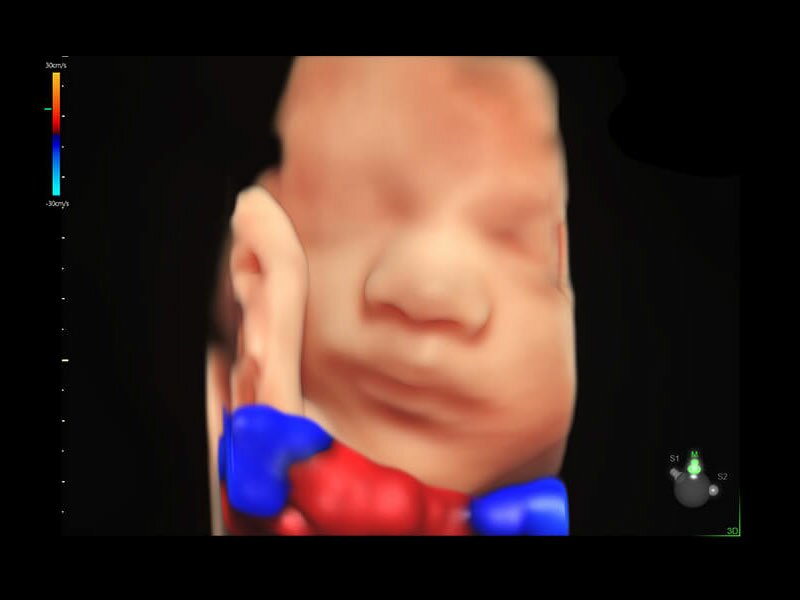

• HDlive Flow - перемещаемый источник света, совместимый с визуализацией кровотока в 3D

• HDlive Flow Silhouette - режим "Силуэт" с выделением границ полостей сердца и сосудов, совместимый с визуализацией кровотока

• Технология HDlive Flow — повышает реалистичность визуализации сосудистых структур, улучшая восприятие глубины (по сравнению с традиционным цветовым допплером и функцией HD-Flow).

• SonoVCAD heart (Sonography-based Volume Computer Aided Display heart) — программа формирует изображения сердца плода в стандартных проекциях в соответствии с международными рекомендациями на основе одного объемного изображения или данных 4D визуализации, полученных методом STIC.